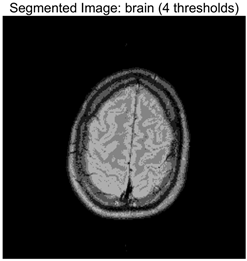

Table 8 presents the distributions of the optimal thresholds selected by each algorithm on the image histograms. Table 9 reports the mean and standard deviation of the best fitness values obtained by each algorithm based on the Otsu objective function, along with their average performance rankings. Furthermore, Table 10, Table 11 and Table 12 summarize the mean, standard deviation, and average ranking of each algorithm in terms of PSNR, FSIM, and SSIM, respectively. The experiments cover four threshold levels (4, 6, 8, and 10), with all results obtained through optimal threshold search using the Otsu criterion.

Table 9 focuses on the optimal fitness values obtained based on the Otsu objective function (maximization of inter-class variance), which directly reflects the algorithms’ ability to search for segmentation thresholds. Higher Ave values indicate that the thresholds are closer to the global optimum, while lower Std values reflect greater consistency across multiple runs. From the data distribution, RLTC-SCA exhibits a dual advantage of “high Ave + low Std” across all image and threshold-level combinations. For instance, in the brain image (a medical brain image with complex grayscale distribution), when TH = 4, RLTC-SCA achieves an Ave value of 3.7306 × 103, comparable to AGPSO and MVO, but its Std value (2.3126 × 10−12) is only 1.53 × 10−11 times that of AGWO (1.5156 × 10−1), showing virtually no fluctuation. At TH = 10, its Ave value (3.7694 × 103) still surpasses standard SCA (3.7644 × 103) and AGWO (3.7691 × 103), with a Std value (1.3312 × 10−1) amounting to merely 3.81% of IVYA (3.4907 × 100), demonstrating stable threshold-search accuracy even at high threshold levels. In the camera image (industrial scene image with low grayscale contrast), at TH = 4, RLTC-SCA’s Ave value (4.6008 × 103) is 0.01% higher than the second-best AGPSO (4.6003 × 103), while its Std value (0.69397) is only 39.44% of standard SCA (1.7594), validating that the reinforcement learning-based action selection strategy can dynamically adjust search actions to avoid threshold selection bias in smooth grayscale distributions. In contrast, algorithms such as IVYA, lacking guided global exploration, show lower Ave values and Std values exceeding 3.0 × 100 in most images, ranking last (8th) in the Friedman ranking, compared with RLTC-SCA ranked 1st.